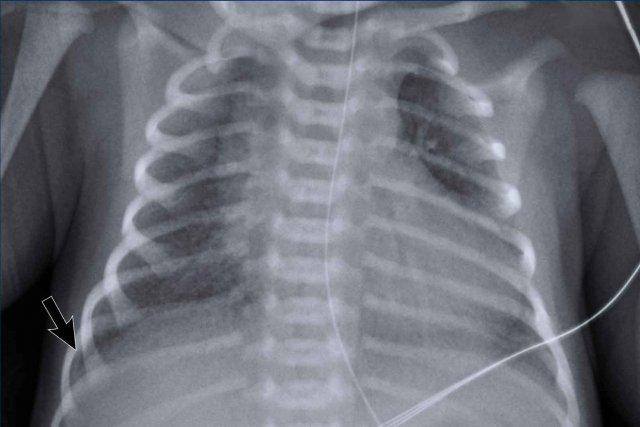

29 tuần + 1, ngày đầu tiên. CPAP.

Findings:

- Reticulogranular opacification

of lungs - Air bronchogram

- Consolidation in the right lower lobe

- Heart, vessels and

diaphragm are poorly defined. - Đặt sai vị trí catheter tĩnh mạch rốn (mũi tên), có thể nằm trong tĩnh mạch phổi.

- Nasogastric tube (NG tube) in good position.

Đây là trường hợp nặng của hội chứng suy hô hấp (RDS).

Chẩn đoán phân biệt bao gồm nhiễm trùng phổi do tình trạng đông đặc không đối xứng.